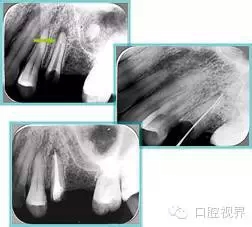

6. 鈣化

常見有修復(fù)性鈣化和增齡性鈣化。下面為根管鈣化 X 線片。

7. 器械折斷

右圖及下圖為器械折斷的 X 線片。箭頭處示折斷器械。